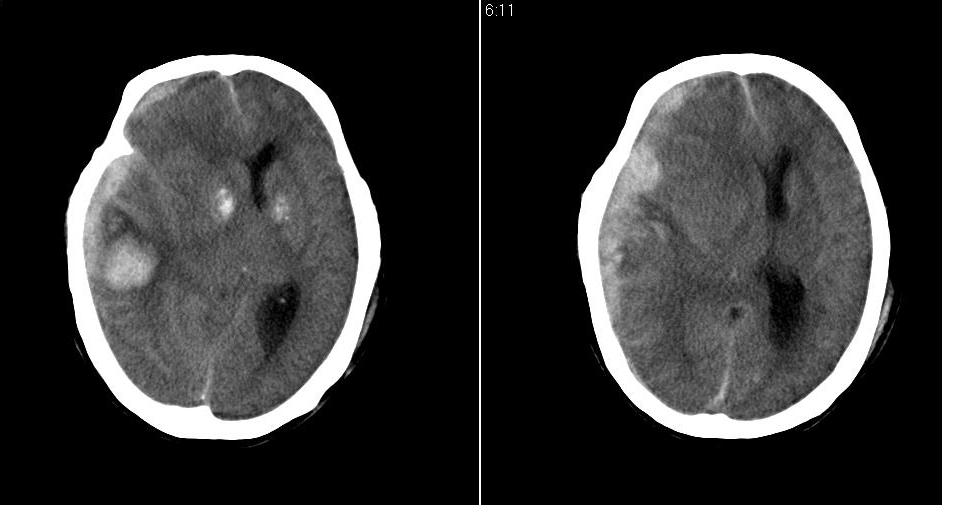

以下是引用川北影像在2007-8-14 15:33:00的发言:[br]1、右侧颞叶脑挫裂伤伴血肿形成。[br]2、右侧额颞顶部硬膜下血肿伴大脑廉下疝形成。

以下是引用gaoshengjiang在2007-8-14 16:30:00的发言:[br]大家都认为右侧颞叶脑挫裂伤伴血肿形成;右侧额颞顶部硬膜下血肿伴大脑廉下疝形成;蛛网膜下腔出血。 但硬膜下血肿、脑内血肿量不多,而大脑廉下疝明显,右侧颞叶类圆形高密度灶,周围轻度水肿,呈蟹足状,考虑脑内占位所致脑内血肿、突然晕倒、硬膜下血肿、颞叶脑挫裂伤等一系列改变。[br][br] [br]

以下是引用拾荒者在2007-8-14 21:59:00的发言:[br][quote]以下是引用gaoshengjiang在2007-8-14 16:30:00的发言:[br]大家都认为右侧颞叶脑挫裂伤伴血肿形成;右侧额颞顶部硬膜下血肿伴大脑廉下疝形成;蛛网膜下腔出血。 但硬膜下血肿、脑内血肿量不多,而大脑廉下疝明显,右侧颞叶类圆形高密度灶,周围轻度水肿,呈蟹足状,考虑脑内占位所致脑内血肿、突然晕倒、硬膜下血肿、颞叶脑挫裂伤等一系列改变。[br][br] [br]